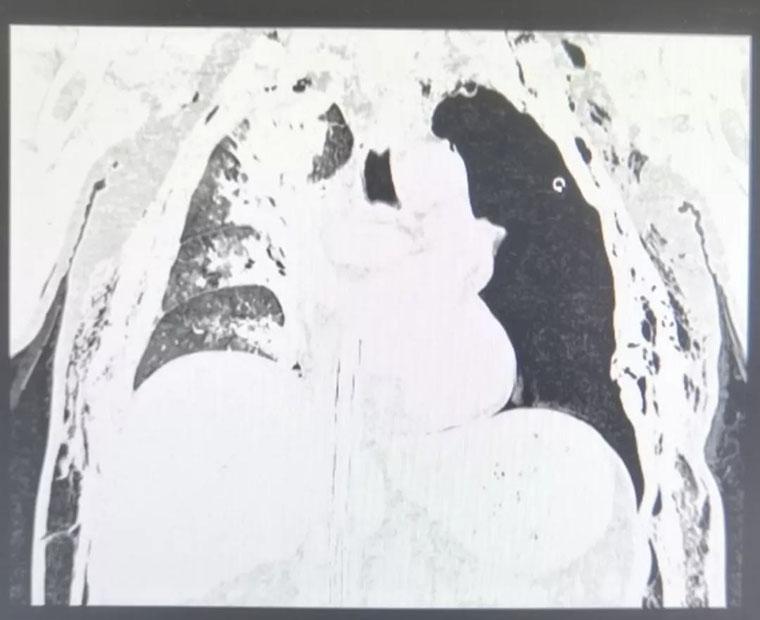

患者的胸部CT

然而,大量的氣泡從胸腔閉式引流管噴出,我們意識到,這樣下去肯定不行,帶ECMO做CT檢查,再次請胸外科會診,討論手術的必要性。